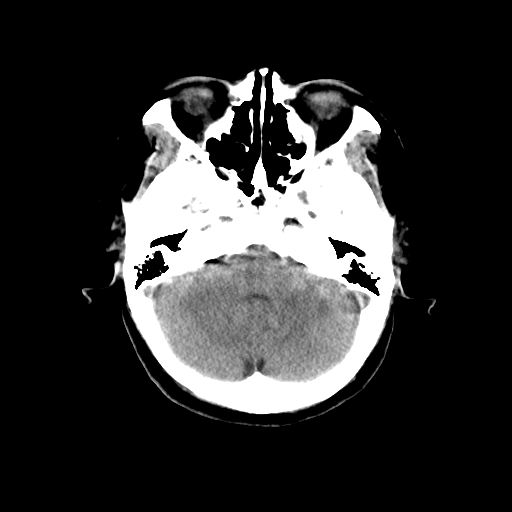

标题: CT14513:女性41岁,头部不适二月余,其它病史不详。请分析 [打印本页]

标题: CT14513:女性41岁,头部不适二月余,其它病史不详。请分析

考虑ii-iii级星形细胞瘤可能性大。

1.考虑:左侧颞顶叶星形细胞瘤。2.大脑镰下疝。